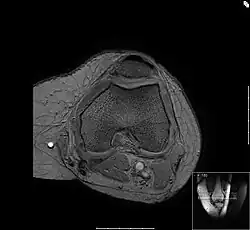

Patellagleitlager

Die Bewegungsprüfung zeigt bei der Chondropathia patellae Reibegeräusche oder ein Knirschen im Gleitlager der Kniescheibe sowie häufig einen Kniescheibenanpressdruck. Der Arzt kann bei der körperlichen Untersuchung bestimmte Phänomene auslösen, die allesamt den Reizzustand des Kniescheibengleitlagers nachweisen. Reizergüsse oder Kapselschwellungen können auftreten, sind aber nicht unbedingt vorhanden. Es gibt eine spezielle Lagerung des Kniegelenkes beim Röntgen, in der das Gleitlager zwischen Kniescheibe und Oberschenkelknochen in verschiedenen Funktionszuständen dargestellt wird, die Aussagekraft ist jedoch begrenzt in Bezug auf die Knorpelschädigung. Gut beurteilt werden kann hingegen die Form des Gleitlagers, also die korrespondierenden Gelenkanteile des Femoropatellargelenkes. Eine ungünstige Kniescheibenform beispielsweise, die sogenannte Patelladysplasie führt zu einer nachteiligen Druckverteilung auf den Knorpel der Kniescheibenrückfläche und stellt somit eine Prädisposition für die Entstehung der Chondropathia patellae dar. Das MRT als weiteres bildgebendes Verfahren zeigt im Gegensatz zur Röntgendiagnostik auch krankhafte Veränderungen des Knorpels selbst.

Femoropatellararthrose

Das Bild zeigt einen Querschnitt durch die Knochen des Oberschenkels, die Femurkondylen. Im oberen Bereich des Bildes liegt die Kniescheibe. Gut zur Darstellung kommt die Feinstruktur des Knochens, die sogenannte Spongiosa.

Zwischen Kniescheibe und dem Oberschenkel ist die Knorpelschicht zu sehen, der feine, graue Saum dazwischen ist die Gelenkflüssigkeit. Im unteren Teil des Bildes ist die Kniekehle mit den durchlaufenden Gefäßen. Die Gelenkkapsel umgibt den Oberschenkel und die Kniescheibe, man sieht angedeutet die Faserstruktur. Das wabige, hell dargestellte Material ist Körperfett.